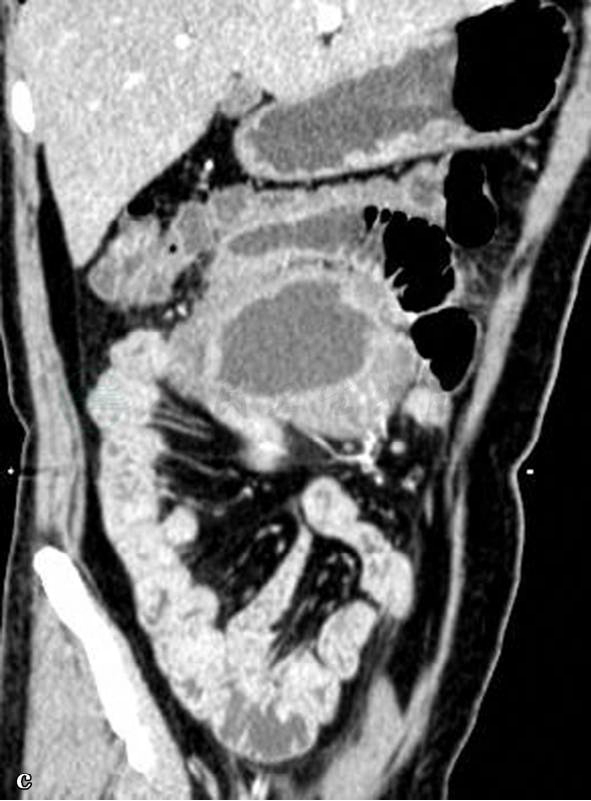

CT平扫、增强扫描及重建图(小肠淋巴瘤)。

图1 图1a,CT平扫图。图1b,CT增强动脉期。图1c,MPR重建图。局部小肠肠壁增厚,但肠腔扩张可见气液平面